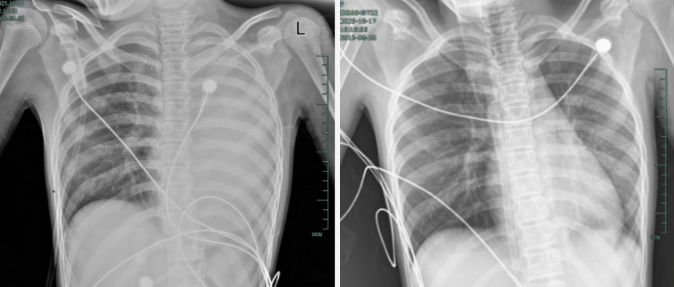

治疗前后影响对比,左肺从“白肺”到正常状态。

呼吸急促、胸闷胸痛,体温38.5℃,只能靠5L/min的面罩吸氧维持血氧,胸片显示左肺已完全呈“白肺”改变,肺部炎症进展迅猛。